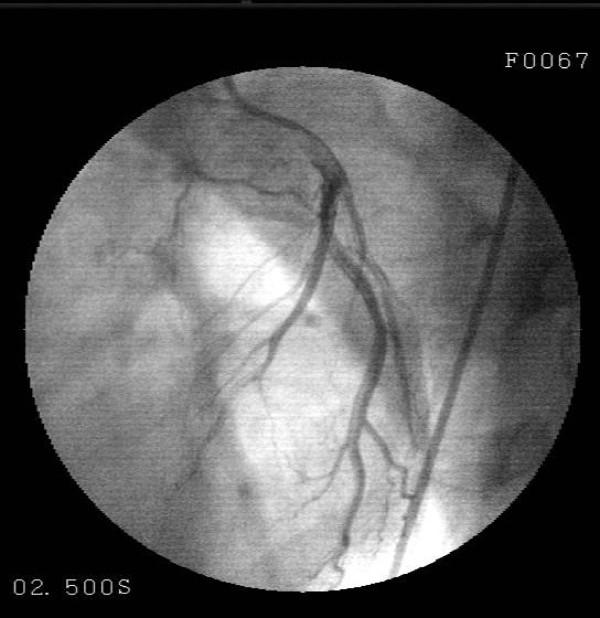

Muscular bridge (MB) is transient systolic coronary blockage occurring due to exposure of a portion of epicardial coronary arteries to compression during systole as a result of tunneling into the myocardium. Although rare, these patients may develop angina pectoris, severe arrhythmia and myocardial infraction (MI). A 30-year-old male patient presented to the emergency with severe pain with an onset at the front part of the chest followed by spreading to the back and arms, during a football match. The investigations performed revealed anterior wall infraction and thus thrombolytic treatment was administered. Patient's history was normal except for smoking. The patient was detected to play football occasionally since his childhood; however, we learnt that he had started playing without warm-up exercises at the last football match. Coronary angiography detected a lesion with an onset in the left anterior descending artery following the 1st diagonal and extending to the 2nd diagonal and exhibiting a significant contraction during systole. The patient was considered to have myocardial infraction secondary to myocardial bridge. Sudden deaths frequently occur in competitive sports requiring heavy effort.

https://cdn.ncbi.nlm.nih.gov/pmc/blobs/1122/2646693/100b73d86c8a/1757-1626-2-135-1.jpg